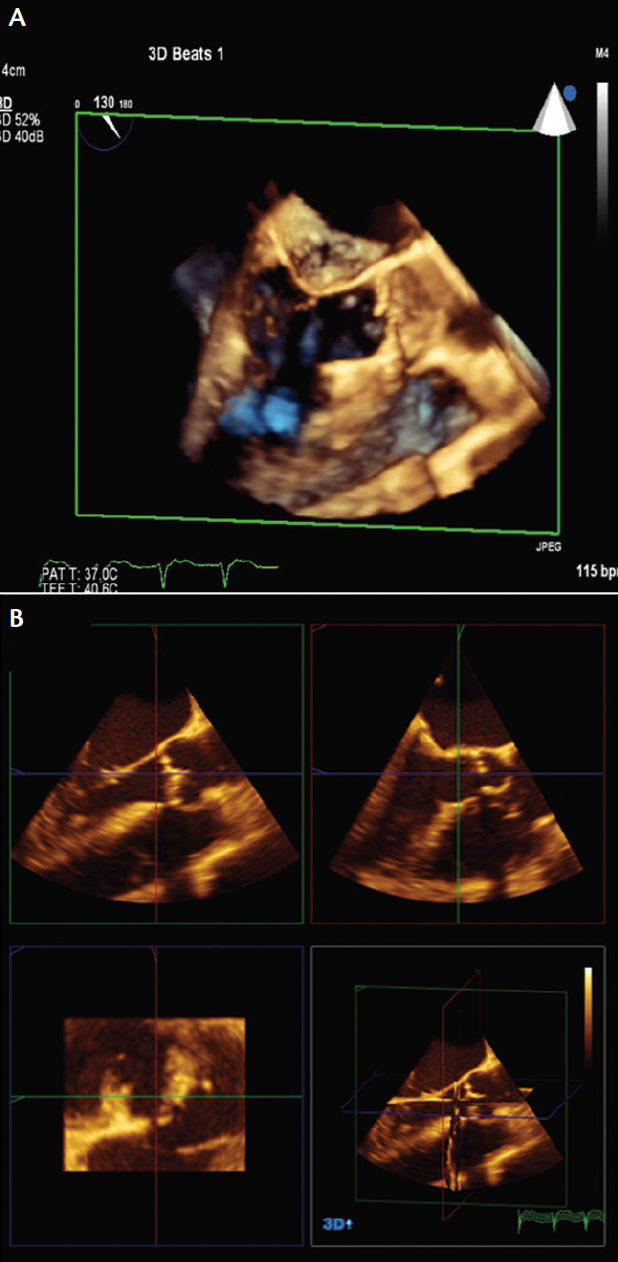

Two-dimensional echocardiography plays a crucial role in transcatheter valve implantation procedures and can also be used in aortic annular sizing. In fact, MDCT and echocardiography may be complementary techniques in this situation. According to the American Society of Echocardiography, the aortic annulus is measured in the parasternal long axis view on transthoracic echocardiography (TTE) or the midesophageal long-axis view on transesophageal echocardiography (TEE).12 The distance is measured between the leaflet insertions of the leaflet on the top of the image to that of the bottom of the image (Figure 1A).

Figure 1. Two-dimensional TEE measurement of the aortic annulus (A). The measurement is made under the aortic valve from the hinge point of one leaflet to another. This measurement should be undertaken in the midesophageal long-axis view of TEE. The orange arrow (B) demonstrates measuring a smaller dimension than what the annulus actually is. This is one of the limitations of 2D TEE annular dimension measurement. The white arrow (B) demonstrates the true sagittal measurement. However, because the annulus is not a perfect circle, the coronal measurement may be larger, again underestimating the annular size. Note that the 2D linear measurement is perpendicular to the long axis of the aorta (C). Biplane imaging across the short axis of the aortic valve may help prevent some of the issues with off-axis measurements of the aortic annulus (D).

The problem with this technique is that measurements made using the leaflet insertions may not transect the full diameter of the aortic annulus; instead, the measurement could be a tangent across the aortic annulus, thus grossly underestimating the annulus size (Figure 1B). When measuring the aortic annulus, care should be taken to exclude or to measure around the significant calcification that can be frequently present along leaflet attachments in patients with severe aortic stenosis. In addition, one must ensure that the measurement of the annular plane is perpendicular to the long axis of the aorta, as this can prevent some of the problems encountered with tangential measurements of the annulus (Figure 1C).

In biplane imaging, bisecting the short axis of the aortic valve produces a longitudinal image and may help in obtaining the largest annular diameter (Figure 1D). This may overcome some of the issues of tangential measurements of the annulus. Despite the limitation of 2D echocardiography for annular sizing, it can give a quick idea of what the appropriate valve size would be for any given patient. For instance, in the case of balloon-expandable valves, a 2D linear measurement of 24 mm would imply the use of a 26-mm valve, and a 2D linear measurement of 27 mm would imply the use of a 29-mm valve.